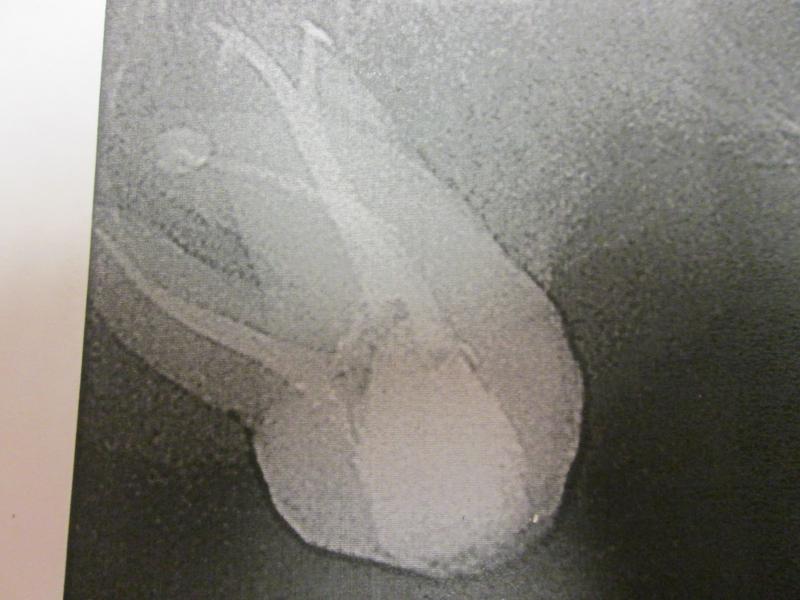

DR JET LOVES ROOT CANALS

"DR. JET'S MISSION IS TO PERFORM  ROOT CANALS FOR A REDUCED FEE USING THE LATEST TECHNOLOGY  AND TECHNIQUES TO SERVICE THE MANY PEOPLE WHO ARE UNINSURED OR UNDER-INSURED GIVING EVERYONE AN OPPORTUNITY TO SAVE THEIR TOOTH!"

ROOT CANALS by DR. JET (Jetepon Chiranand DDS)